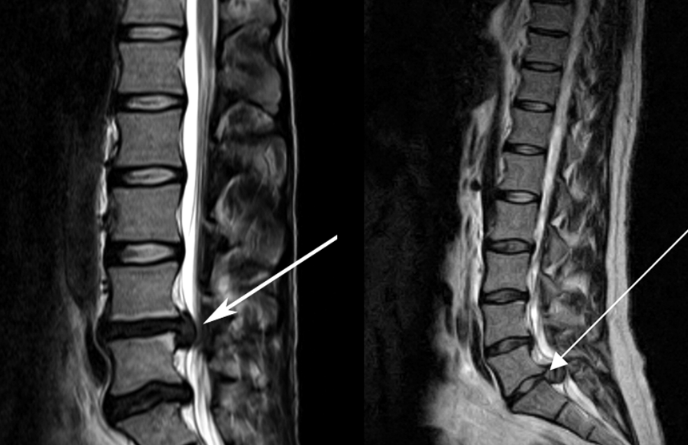

![]() 關于腰椎間盤突出 ![]() 腰椎間盤突出癥是纖維環(huán)破裂后髓核突出壓迫神經根造成以腰腿痛為主要表現的疾病。腰椎間盤退行性改變或外傷所致纖維環(huán)破裂,髓核從破裂處脫出,壓迫腰椎神經,從而出現腰腿放射性疼痛。 ![]() 病因: 一、退行性變: 目前認為,其基本病因是腰椎間盤的退行性變。退行性變是一切生物生、長、衰、亡的客觀規(guī)律,由于腰椎所承擔的特殊的生理功能,腰椎間盤的退行性變比 其他組織器官要早,而且進展相對要快。這個過程是一個長期,復雜的過程。所謂腰椎間盤退行性改變:即由于椎間盤受體重的壓迫,加上腰部又經常進行彎曲、后伸等活動,易造成椎間盤的擠壓和磨損,尤其是下腰部的椎間盤,從而產生退行性改變。腰椎間盤退行性改變是本病發(fā)生的基礎?!?/p> 二、其他因素: 1、外力作用:在日常生活和工作中,部分人往往存在長期腰部用力不當、過度用力姿勢或體位的不正確等情況。例如長期從事彎腰工作的煤礦工人和建筑工人需經常彎腰提舉重物。這些長期反復的外力造成的損傷日積月累地作用于椎間盤,加重了退變的程度。 2、椎間盤自身解剖因素的弱點: (1) 椎間盤在成人之后逐漸缺乏血液循環(huán),修復能力也較差,特別是在退變產生后,修復能力更加微弱。 (2) 椎間盤后外側的纖維環(huán)較為薄弱,而后縱韌帶在腰5、骶1平面時寬度顯著減少,對纖維環(huán)的加強作用明顯減弱。 (3) 腰骶段先天異常:腰骶段畸形可使發(fā)病率增高,這些異常造成椎間隙寬度不等,并常造成關節(jié)突出,關節(jié)受到更多的旋轉勞損,使纖維環(huán)受到的壓力不一,加速退變。 3、種族、遺傳因素:有色人種發(fā)病率較低,例如印第安人和非洲黑人等發(fā)病率較其他民族明顯要低。 ![]() 2 病理 腰椎間盤突出癥的病理變化過程大致可分為三個階段: 1、突出前期:髓核因退變和損傷可變成碎塊狀物,或呈瘢痕樣結締組織,變性的纖維環(huán)可因反復損傷而變薄變軟或產生裂隙。此期病人可有腰部不適或疼痛,但無放射性下肢痛。也有的人原無病變,可因一次大的暴力引起髓核突出。 2、突出期:外傷或正常的活動使椎間盤壓力增加時,髓核從纖維環(huán)薄弱處或破裂處突出。突出物刺激或壓迫神經根即發(fā)生放射性下肢痛,或壓迫馬尾神經發(fā)生大小便功能障礙。在老 年患者,可因椎間盤退變,整個纖維環(huán)變得軟弱松弛,椎間盤可呈彌漫性向周圍膨出。 3、突出晚期:腰椎間盤突出后,病程較長者,椎間盤本身和其他鄰近結構均可發(fā)生各種繼發(fā)性病理改變。 3 誘發(fā)因素 腰椎間盤突出癥的基本因素是椎間盤退變,但某些誘發(fā)因素可致使椎間隙壓力增高,引起髓核突出。此種誘發(fā)因素常與以下因素有關: 1. 年齡因素:腰椎間盤突出癥的好發(fā)年齡在30-50歲,平均手術年齡在40歲,因此退變可能是其重要因素。 2. 身高與性別:有人認為身材過高也會易發(fā)腰突癥,而男性發(fā)病率是女性的5倍。 3. 增加腹壓:臨床上有約1/3的病人在發(fā)病前有明確的增加腹壓的因素,如劇烈的咳嗽、噴嚏、屏氣、用力排便等。使腹壓增高,破壞了椎節(jié)與椎管之間的平衡狀態(tài)?!?/p> 4. 不良體位:人在完成各種工作時,需要不斷更換各種體位以緩解腰部壓力,如長期處于某一體位不變,即可導致局部的累積性損傷。特別是長期處于不良姿勢更容易誘發(fā)本病。 5. 職業(yè)因素:重體力勞動者發(fā)病率最高,白領勞動者最低。汽車駕駛員由于長期處于顛簸和振動狀態(tài),椎間盤承受的壓力大且反復變化,也易誘發(fā)椎間盤突出?!?/p> 6. 受寒受濕:寒冷或潮濕可引起小血管收縮、肌肉痙攣,使椎間盤的壓力增加,可能造成退變的椎間盤破裂。 ![]() ![]() ![]() ![]() 癥狀: 腰椎間盤突出癥患者最多見的癥狀為疼痛,可表現為腰背痛、坐骨神經痛,典型的坐骨神經痛表現為由臀部、大腿后側、小腿外側至跟部或足背的放射痛。據臨床統計,約95%的腰突癥患者有不同程度的腰痛,80%的患者有下肢痛。特別是腰痛,不僅是腰椎間盤突出最常見的癥狀,也是最早出現的癥狀之一。 ![]() ![]() ![]() 檢查: 1、X線:腰椎間盤所包括的髓核、纖維環(huán)和軟骨板密度均較低,在X線下并不顯影,因此臨床上腰突癥患者的腰椎X線平片可僅有一些非特異性的變化,甚至無異常變化。因此單純腰椎平片并不能作為有無腰椎間盤突出癥的直接依據,但X線能發(fā)現腰椎的退行性改變和結構異常,對提示椎間盤的退變有重要意義,并且能排除其他的一些腰椎疾患,如腰椎結核、腫瘤和腰椎滑脫等。典型的腰椎間盤突出癥患者通過病史、體征和X線平片即能作出初步的診斷?!?/p> 2、CT檢查:腰椎的CT可以清楚地顯示椎間盤突出的部位、大小、形態(tài)和神經根、硬脊膜受壓的情況,同時還可顯示黃韌帶肥厚、小關節(jié)增生、椎管和側隱窩狹窄等情況。對腰椎間盤突出癥診斷的準確率達到80%-92%?!?/p> 3、核磁共振(MRI):核磁共振沒有輻射,可以多方位成像(橫斷面、冠狀面、矢狀面和斜面),對解剖細節(jié)顯示較好,對組織結構的細微病理變化更敏感(如骨髓的浸潤),可以排除神經和脊柱腫瘤等。對于一些落到椎管的髓核組織也不會遺漏?!?/p> 4、脊髓造影:脊髓造影利用椎管內蛛網膜下腔的空隙,注入造影劑后在X線下攝片,顯示椎管內部結構。目前常用水溶性造影劑,能較清晰地顯示硬膜腔、馬尾神經和神經根鞘,對腰椎間盤突出癥的診斷可達90%左右,主要X線表現為硬膜囊壓迫征象和神經根鞘壓迫征象。但由于CT和MRI在臨床的廣泛應用,無創(chuàng)傷且診斷率更高,脊髓造影在臨床上的應用已經大大減少,而且由于它副作用較大,甚至可能造成截癱等嚴重情況,目前主張慎重選用。 5、肌電圖:肌電圖是對周圍神經與肌肉的電生理檢查方法,可用于觀察并記錄肌肉在靜止、主動收縮和支配其的周圍神經受刺激時的電活動,同時也可用來測量周圍神經的傳導速度。在腰椎間盤突出癥上,肌電圖主要通過檢查雙下肢肌肉的興奮性來反映相應神經根的狀態(tài),并根據異常電活動的分布范圍來判斷椎間盤突出和神經根受壓的節(jié)段。在脊神經根和馬尾神經受壓的病人,肌電圖陽性率可達80%-90%,但與CT和MRI相比并不是首選的檢查手段,可用于輔助診斷和判斷神經根的受壓情況,同時也可以用來作為判斷治療后神經根恢復情況的指標之一。 ![]() ![]() ![]() 預防: 腰椎間盤突出癥是在退行性變基礎上積累傷所致,積累傷又會加重椎間盤的退變,因此預防的重點在于減少積累傷。 日常注意事項: 1.平時要有良好的坐姿,睡眠時的床不宜太軟。 2.長期伏案工作者需要注意桌、椅高度,定期改變姿勢。 3.職業(yè)工作中需要常彎腰動作者,應定時伸腰、挺胸活動,并使用寬的腰帶。 4.應加強腰背肌訓練,增加脊柱的內在穩(wěn)定性,長期使用腰圍者,尤其需要注意腰背肌鍛煉,以防止失用性肌肉萎縮帶來不良后果。 5.如需彎腰取物,最好采用屈髖、屈膝下蹲方式,減少對腰椎間盤后方的壓力。 ![]() ![]() ![]() 治療: (一)中醫(yī)外敷療法: 腰椎間盤突出可以外貼 腰突正骨膏,其有效成分可透入皮膚產生活血,止痛,化淤,通經走絡,開竅透骨,祛風散寒等效果,并通過藥物的歸經作用而調理機體陰陽平衡,滲透于表皮,刺激神經末梢,促進局部血液微循環(huán),扶正固本、改善體質,從根本上、全方位針對腰椎疾病病機特點而發(fā)揮療效,改善病變周圍組織營養(yǎng),起到修復骨病組織的作用,最終達到治療目的。 (二)自我治療: 1.腹肌鍛煉: 也就是仰臥起坐。每次做十個,每天三次。(可根據患者的體質來定,不可逞強)。 2.交叉扭腰: 兩腳分開與肩寬,腳尖向內兩臂伸直,一手在體側,一 手舉過頭頂。如果右手在上,先向左側后方擺。左側相反。于此同時腰部也隨之扭動,左右各100次。 3.抱膝觸胸: 處于仰臥位,雙膝屈曲,手抱住膝部,使盡量靠近胸部,然后放下,一上一下為一個動作,可持續(xù)30個。 4.腰背肌鍛煉: 處于平臥,雙膝彎曲放在床上,然后用力將臀部抬起,離開床面10厘米。這時您會感覺到腰背部在用力,堅持5秒鐘,反復10下。 ![]() (三)非手術治療: 非手術療法是治療腰椎間盤突出癥的基本療法,約80%以上的患者經保守治療均可得到緩解和痊愈。其主要療法有: 1.日常家庭治療:早期腰椎間盤突出癥,癥狀輕微,不需要做特殊的治療。第一,注意臥床休息,避免腰椎受外力壓迫,第二,應用其他方法積極鍛煉腰部肌肉力量。 2.牽引治療; 3.推拿按摩治療; 4.物理治療; 5.消炎鎮(zhèn)痛藥物; 6.減輕神經根水腫藥物。 (四)推拿治療: 1.解除腰臀部肌肉痙攣 2.拉寬椎間隙,降低盤間壓力 3.增加椎間盤外壓力 4.調整后關節(jié),松解粘連 5.促使受損傷的神經根恢復功能 (五)微創(chuàng)治療: 微創(chuàng)治療方法的目的是消除腰椎間盤突出的髓核以解除對神經的壓迫。微創(chuàng)治療技術采用可視設備,創(chuàng)口不足一厘米有些甚至不足一毫米。消融或摘除髓核,從根本上解除致病因素,因而能夠取得很好的效果。 (六)手術治療: 腰椎間盤突出癥的手術原則是嚴格無菌操作,盡量保留不必去除的骨結構和軟組織結構,以最小的創(chuàng)傷達到足夠的顯露,仔細徹底地去除病變組織,達到治療目的。 ![]() ![]() 綠柏相關產品: ![]() 懸吊訓練療法是康復醫(yī)學中以持久改善肌肉骨骼疾病為目的的,應用主動治療和訓練的一個總的概念整合,是一種運動感覺的綜合訓練系統,包括診斷與治療兩大系統。 產品特點: 1.電腦軟件管理系統,涵蓋患者信息管理、評估、訓練、量表、報告、視頻教學六大模塊,輕松實現評估與訓練一體化管理; 2.多點多軸設計,滿足不同治療方案設計; 3.懸吊工作站及各個懸吊點,均能實現任意位置移動,一鍵解鎖,省時省力; 4.實時力反饋,精準量化弱鏈測試及懸吊治療全過程,給治療師及患者最直觀的效果呈現; 5.智能神經肌肉促通裝置,可根據評估結果設置治療模式、頻率、時間等相關參數,讓懸吊康復更加高效有針對性; 6.外觀高端大氣,結構穩(wěn)固,給患者安全保障,增加治療信心。 ![]() |